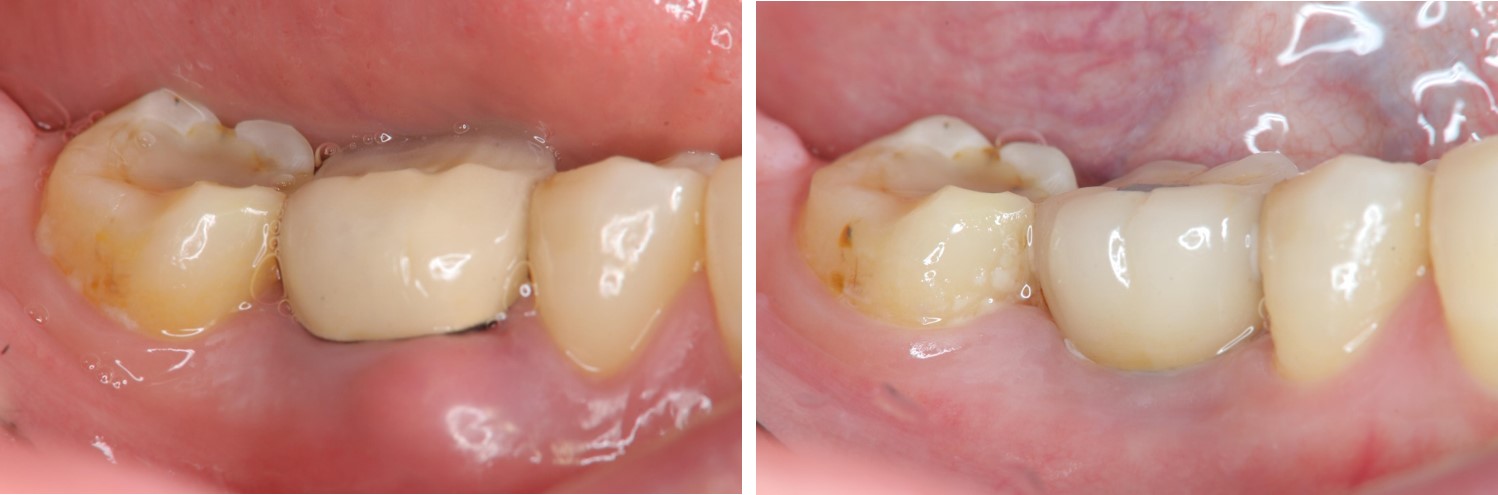

治療後,咬合牙周適應良好

治療後,密合度良好

術前、術後比較